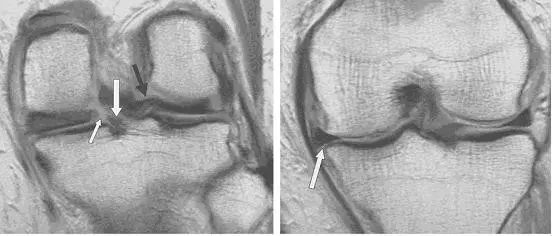

图 2 正常半月板

左图:外侧半月板,由于横截面面积一致,故在MRI 上可见外侧半月板前后角(纵向白色箭头)形状和大小较相似。上下腘肌半月板纤维束(黑色箭头)在外侧半月板后角处,形成裂孔,中间有腘肌腱(水平白色箭头)通过。右图:内侧半月板,可见后角(白色圆箭头),略大于前角(白色直箭头)